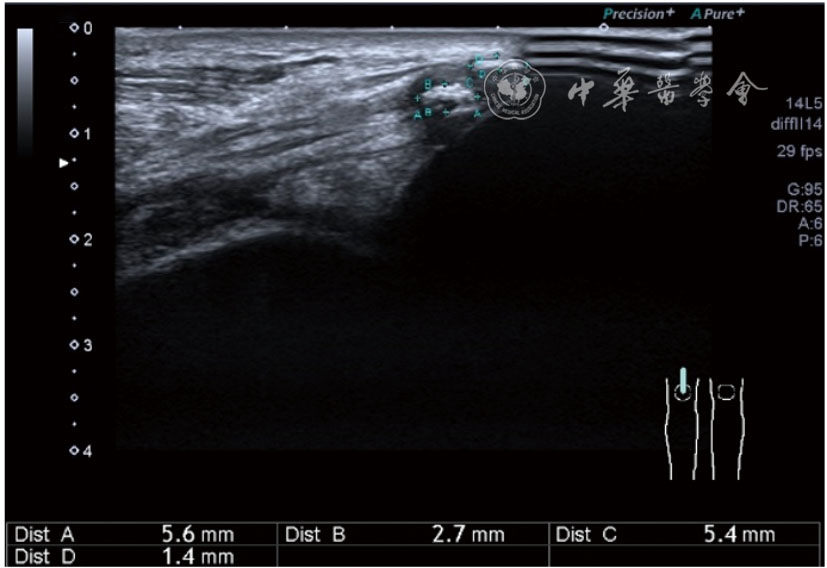

2.腓总神经卡压静态结构针刀切割松解治疗。体位与治疗前准备同局部液压松解加药物注射治疗。治疗点在卡压最明显的部位,一般有两个部位,一是入腓骨长肌前,腘肌与股二头肌筋膜构成的纤维通道;二是腓总神经进入腓骨长肌内的腓骨长肌筋膜。(1)入腓骨长肌前腓管针刀切割松解治疗。找到腓总神经卡压最明显处,应用25G注射针头抽吸0.5%利多卡因6~8 ml,从近端穿刺,沿腓总神经长轴在筋膜与神经之间注射,分离扩张腓管,满意后用直径1.0 mm的Ⅰ型2号针刀由近端向远端平面内进刀,由浅入深切割分离的腓管筋膜,直至松解彻底拔出针刀(图40),局部压迫止血5分钟,无菌敷料覆盖。(2)入腓骨长肌腓管针刀切割松解治疗。长轴找到腓总神经卡压最明显处,将探头转为短轴,应用25G注射针头抽吸0.5%利多卡因6~8 ml,于腓管筋膜表面和筋膜与神经之间注射,分离扩张腓管,满意后用直径1.0 mm的Ⅰ型2号针刀由后向前平面内进刀,由浅入深切割分离的腓管筋膜,直至松解彻底拔出针刀(图41),局部压迫止血5分钟,无菌敷料覆盖。

图41 超声引导下入腓骨长肌腓管针刀切割松解治疗